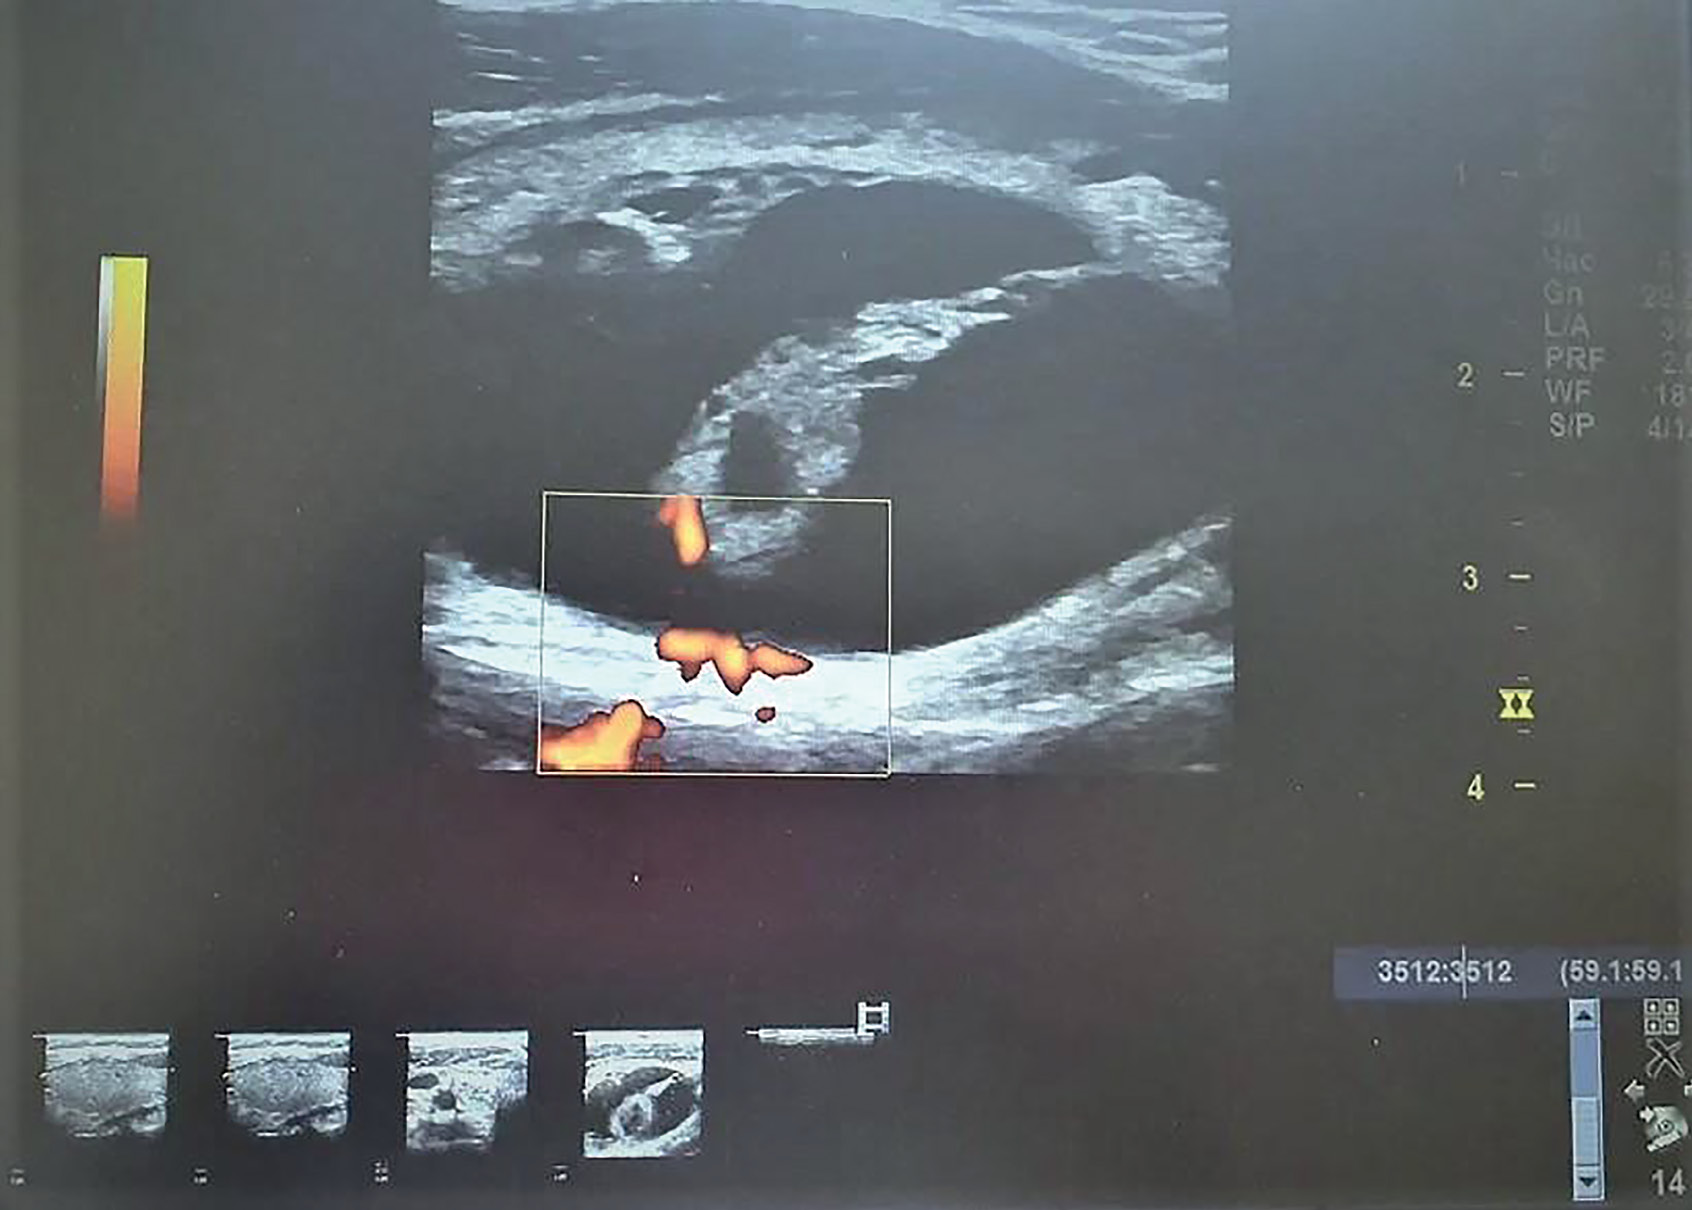

|  | 1. Рисунок 1. Узловое образование щитовидной железы с четкими ровными контурами и выраженным анэхогенным компонентом (EU-TIRADS 2). | |